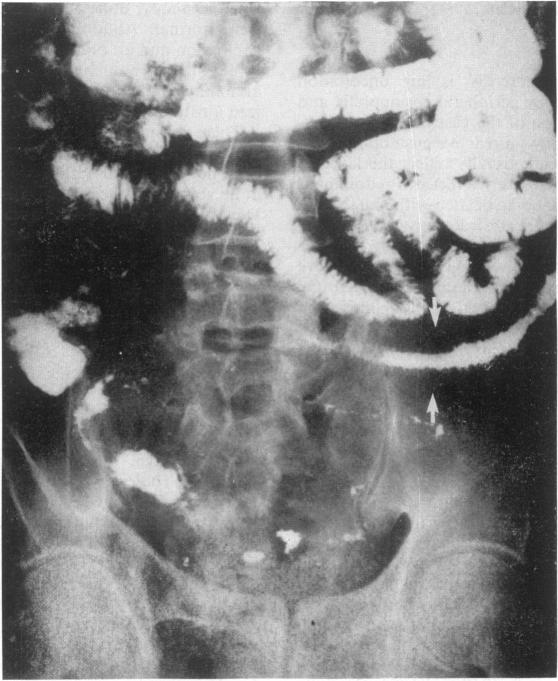

A 65-year-old man with a 20-year history of recurrent abdominal pain and vomiting was found to have eosinophilic enteritis affecting the muscularis layer of the distal ileum. Tests for malabsorption were negative. The IgE was raised but there was no evidence of an allergic predisposition. The symptoms, eosinophilia, and radiological abnormality responded to oral disodium cromoglycate.

一名65岁男性,有20年复发性腹痛和呕吐病史,被发现患有嗜酸性粒细胞性肠炎,累及回肠末端肌层。吸收不良检查结果为阴性。免疫球蛋白E升高,但无过敏倾向证据。口服色甘酸钠后,症状、嗜酸性粒细胞增多及放射学异常均有改善。